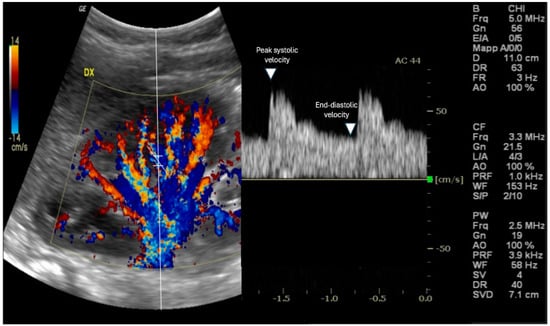

2. Measuring RRI: Methodology